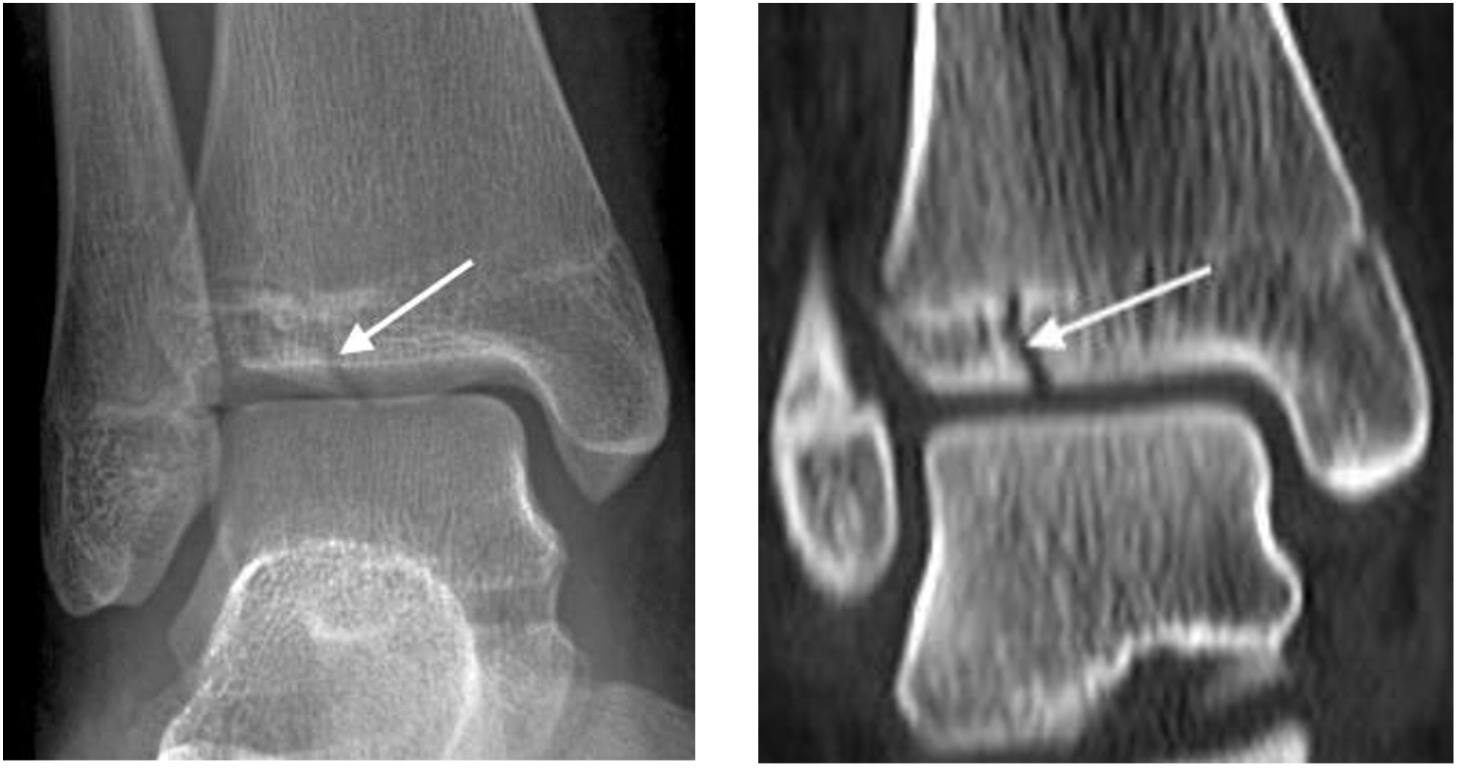

Triplanar fracture

- Salter-Harris type 4 fracture through the lateral distal tibia with sagittal, axial and coronal plane components

- Comprises a vertical fracture through the epiphysis, horizontal fracture through the physis and oblique fracture through the metaphysis

Triplanar fracture extending through the distal tibial epiphysis, physis and metaphysis (arrows)